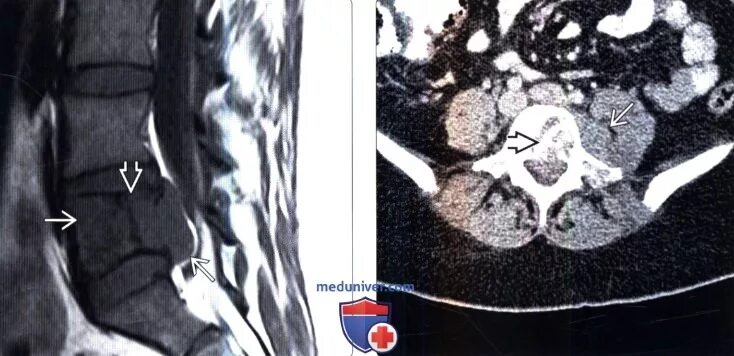

Метастазы костей мрт